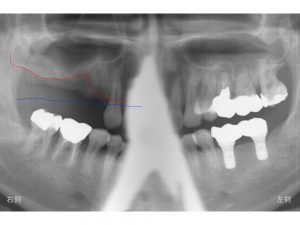

以下の青線は、元々の骨があった位置です。

骨吸収する前はだいたいこの位置まで骨があったと考えて下さい。

以下の写真の赤線は現在の骨の位置です。

歯周病等問題のある状態が長くあったため、

歯を支えていた骨が吸収(溶けて)しまったのです。

これだけ骨吸収を起こすとインプラント治療を難しくします。

以下は上顎洞の空洞の下の線です。

上顎洞底といいます。

緑色で表示します。

現在ある骨の高さは赤線と青線の間ということになります。

前歯に近い欠損部には骨の高さはある程度残っています。

しかし、その奥になると骨吸収が大きくなり、骨の残っている高さは非常に少なくなります。

さらにその奥も骨吸収が大きいため、骨の高さは非常に少ないです。

一番奥歯については、骨の高さは少ないですが、ある程度残っています。